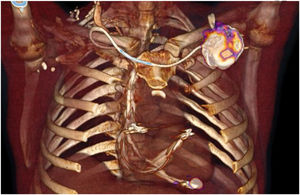

Tomografía por emisión de positrones/tomografía computarizada con 18F-FluorodesoxiglucosaEl uso del [18F]FDG-PET/TC que fue incorporado como criterio mayor de endocarditis infecciosa protésica en las últimas guías de práctica clínica2, también ha demostrado su capacidad para detectar émbolos sépticos a distancia 21. Se postula que puede ayudar a la localización anatómica de la infección de DEC. Recientes revisiones publicadas en la literatura contemplan el uso del [18F]FDG-PET/TC en el algoritmo diagnóstico por su alta sensibilidad y especificidad, para las infecciones localizadas del bolsillo del generador (fig. 4)12. Sin embargo, para los segmentos endovasculares e intracardiacos el rendimiento diagnóstico de esta técnica es menor (tabla 2).